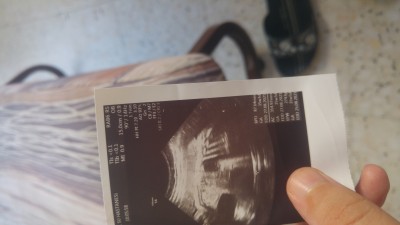

Ultrosyon kagdiindan anlayan

Anlayan varmi

46 cm 2354 gram.

İyimi peki normalmi

Gayet uyumlu haftasıyla. Yanlış görmüyorsam 33 haftalık yazıyor. Hatta 34 olmak üzere

Boyunu nasıl anladınız

FL yazan değer var, onu 7 ile çarpıyorsunuz boyu için. Sizinki mm cinsinden tabii, önce cm'ye çevirdim